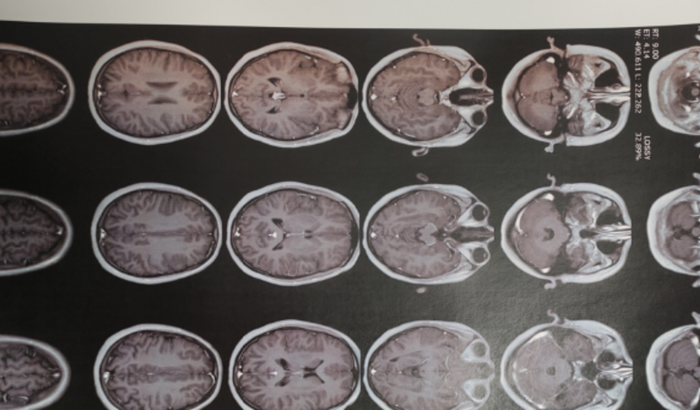

Eu, Paula, criei essa vakinha pra tentar suprir os exames necessários pra eliminar o tumor, e os os problemas neurológicos que custam muito alto, preciso de mais uma ressonância, e infelizmente tem mais gastos com endocrinologista, qualquer valor ajudaria. Qualquer ajuda ou divulgação ajudaria.